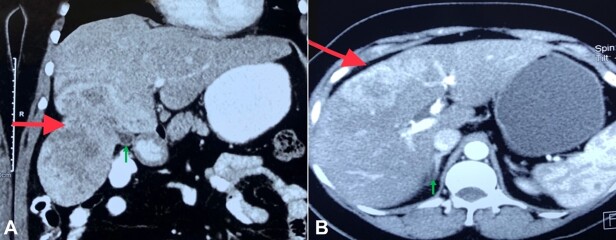

Biliary adenofibroma (BAF) is an uncommon liver tumor with a high propensity for malignant transformation. The histomorphology of BAF with malignant transformation can show a spectrum of changes ranging from benign, dysplastic to frank malignancy. Thus, the diagnosis of BAF imposes the pursuit of dysplasia/ malignancy focus. We presented a case of intrahepatic cholangiocarcinoma arising from BAF in a 49-year-old woman with detailed histomorphology. We also performed a PubMed database search and tabulated all previously reported cases of BAF with dysplasia/ malignant transformation. A statistic comparison of age, sex ratio, size of the tumor, and survival following complete resection between BAFs with and without dysplasia/ malignancy from the retrieved data is presented. Our analysis did not highlight any statistically significant difference between BAFs with and without dysplasia/ malignancy in age, sex ratio, tumor size, and survival following complete surgical resection. Our study highlights the histopathology and immunohistochemistry of a case of BAF with malignant transformation and highlights the importance of this diagnosis in management. Further longitudinal studies on a larger cohort of patients are required to validate our findings.